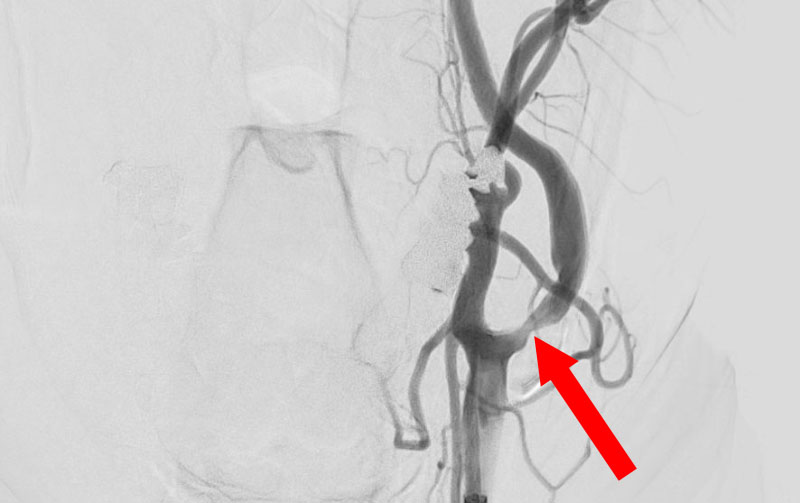

1619

'26年3月11日

左内頚動脈狭窄症

70代

大阪府の病院

手術写真

中

治療

後